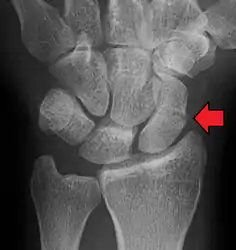

| An X-ray showing a fracture through the waist of the scaphoid | |